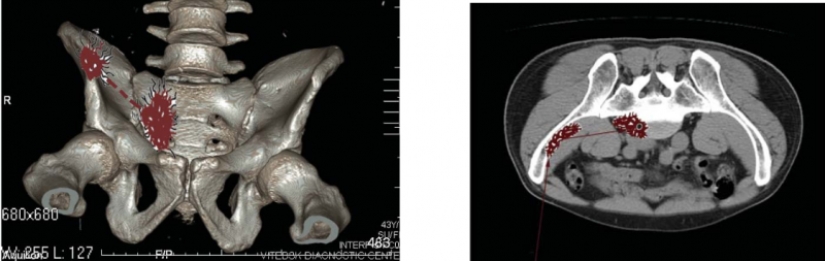

Así es exactamente como se vería la herida de Pushkin en una foto tomada con equipos modernos